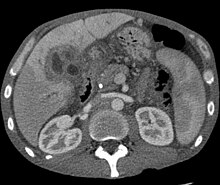

CT scan showing cholangiocarcinoma

Ultrasound of the liver and biliary tree is often used as the initial imaging modality in people with suspected obstructive jaundice.[49][50] Ultrasound can identify obstruction and ductal dilatation and, in some cases, may be sufficient to diagnose cholangiocarcinoma.[51] Computed tomography (CT) scanning may also play an important role in the diagnosis of cholangiocarcinoma.[52][53][54]